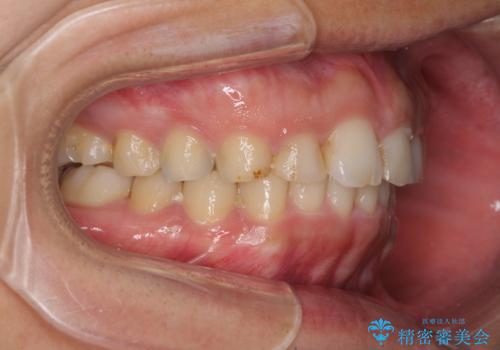

矯正治療とインプラント治療を同じ歯科医師が担当することで、通常見られるような複数医院を行き来する煩雑さや、複数担当医の見解の違いによる治療の遅滞といった煩わしさは一切なく、スムーズに治療を進めることができました。

安定して咬めるようになり、患者様には大変満足していただきました。